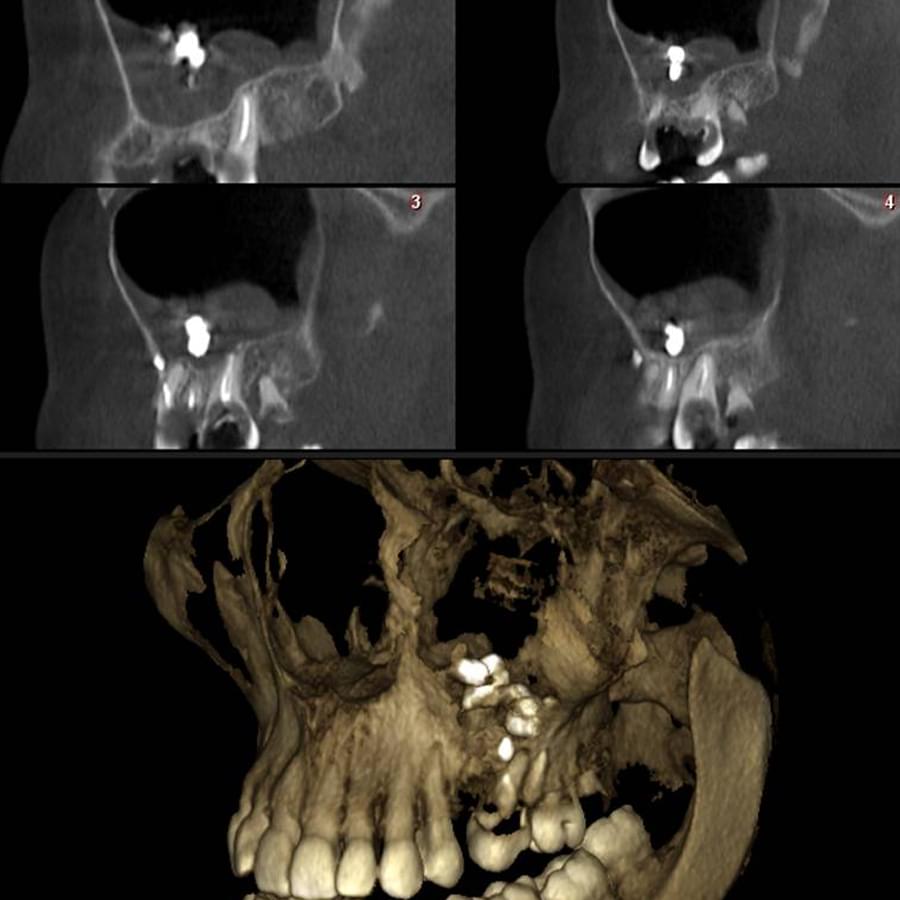

3D цефалометричний аналіз є сучасною технологією, яка дозволяє отримувати точніші,

комплексніші та надійніші дані про зубну та скелетну структуру. Ця технологія може стати

великим кроком в перед для ортодонтів, які хочуть забезпечити найкраще можливе лікування

своїх пацієнтів.

Основні переваги 3D цефалометричного аналізу:

Точність: 3D цефалометричний аналіз забезпечує точніше визначення розмірів та відстаней між

зубами та кістковими структурами.

Комплексність: ця технологія дозволяє отримувати детальні дані про різні структури, такі як

кістка та м'язи, що дозволяє ортодонтам докладніше досліджувати деякі патології та планувати

лікування.

Надійність: 3D цефалометричний аналіз дозволяє отримувати надійніші результати, оскільки

виключає можливість помилок, пов'язаних зі спотворенням або перекриттям зображень.